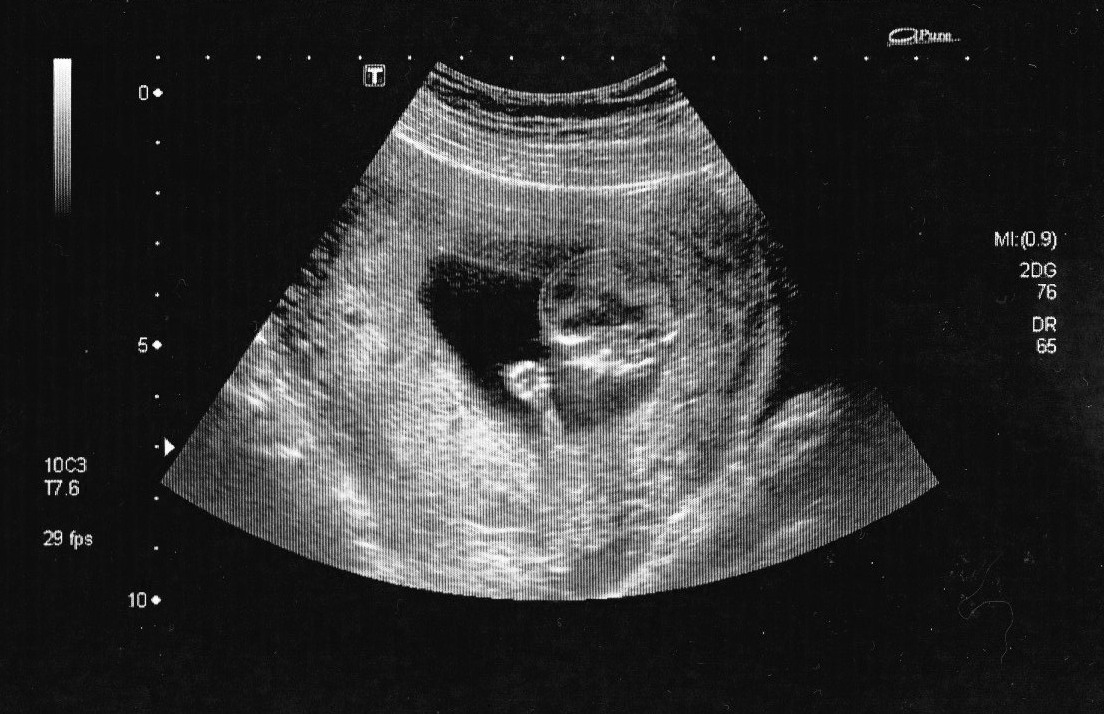

Echo 3 mois

BBChou mesure 5.91 cm

La petite main de BBChou